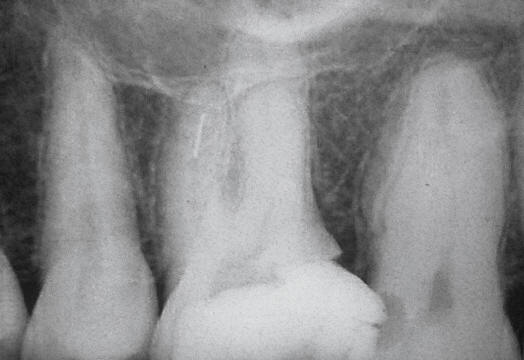

Se selecciona el instrumento

ultrasónico, según la profundidad a la que se encuentra

el fragmento y el espacio disponible. Este instrumento

se activa a la potencia mínima y se utiliza en seco,

para obtener una visión constante de la punta

funcionando y del instrumento roto.

El instrumento seleccionado se

mueve ligeramente alrededor del instrumento en sentido

antihorario. Por lo general durante el uso del

ultrasonido el fragmento comienza a aflojarse,

desenroscarse y girar. La mayoría de los instrumentos de

acero inoxidable y carbón se desplazan en dirección

coronal si se establece alrededor de ellos un plano de

socavamiento de 1,5-2 mm y a continuación se activa el

fragmento con energía ultrasónica (34). Si se ejerce una

suave acción de palanca con la punta entre la lima y la

pared del conducto, en ocasiones el instrumento "salta"

del interior del mismo (2).